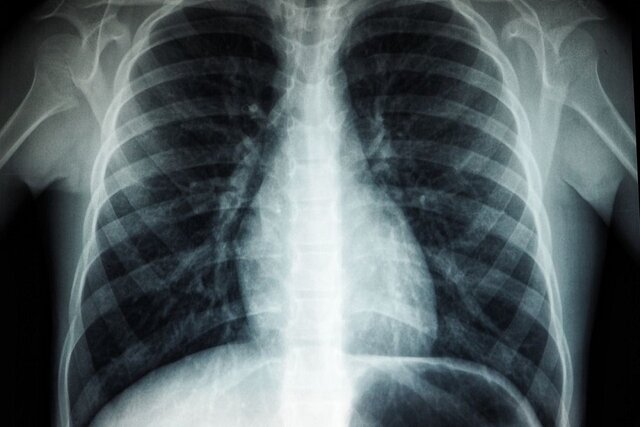

تقریبا ۵۰ درصد از بیماران سرطانی پرتودرمانی می‌شوند و پرتودرمانی نیز یک روش درمانی است که در آن از ذرات باردار الکتریکی برای کشتن سلول‌های سرطانی استفاده می‌شود. حدود ۴۰ درصد از بیماران با این روش درمانی بهبود می‌یابند. با این حال، آسیب به استخوان یک عارضه جانبی است که بر روی ۷۵ درصد از بیمارانی که پرتودرمانی دریافت می‌کنند، تاثیر می‌گذارد.

کواتاپ گفت: استخوان به دلیل محتوای کلسیم بالای آن، ۳۰ تا ۴۰ درصد بیشتر از سایر بافت‌ها تشعشعات را جذب می‌کند و بنابراین یک محل آسیب پذیر است. پرتوهای حاصل از پرتودرمانی، استخوان را شکننده می‌کند و پس از آن استخوان به راحتی می‌شکند و به دلیل آسیب ناشی از تشعشع، بسیاری از افراد قادر به ترمیم شکستگی استخوان خود نیستند. در برخی افراد، این امر به قطع عضو برای رفع عارضه منجر می‌شود.

در حالی که پرتوهای حاصل از پرتودرمانی مستقیما به سمت تومور قرار می‌گیرند، بافت سالم اطراف آن نیز آسیب می‌بیند و می‌تواند بسیاری از مشکلات سلامتی را برای بیماران ایجاد کند.